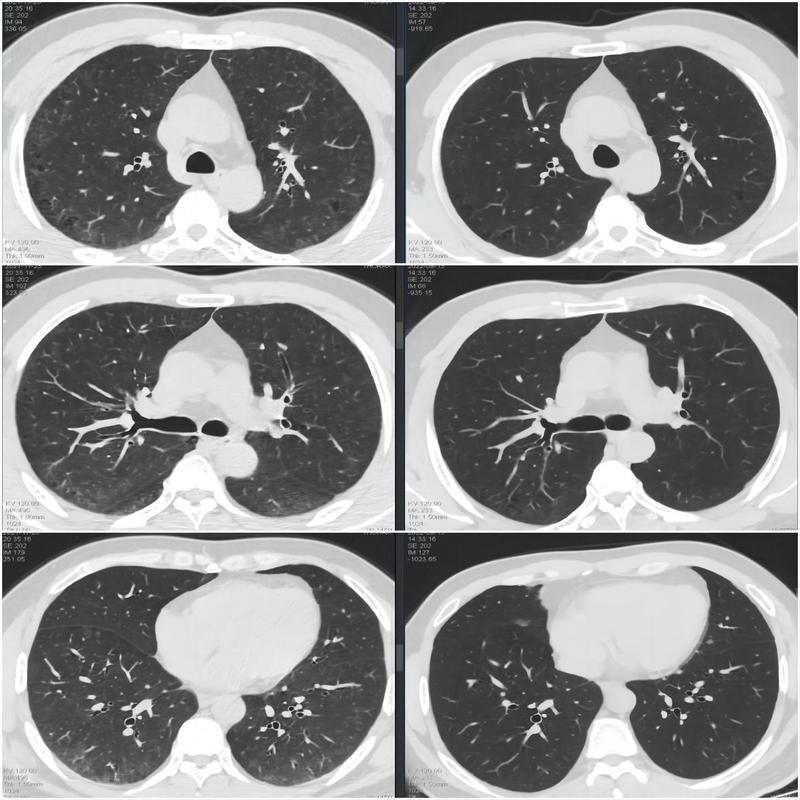

間質(zhì)性肺病的病例分享

???????間質(zhì)性肺病是指由許多已知或未知原因引起的一組彌漫性肺疾病的總稱,累及肺泡及其周圍的間質(zhì)組織,造成肺組織正常結(jié)構(gòu)發(fā)應(yīng)甚至結(jié)構(gòu)破壞,形成進(jìn)行性發(fā)展的瘢痕。這些瘢痕(即纖維化)最終會(huì)影響呼吸功能,不僅肺的體積縮小,吸到肺部的氣體減少,而且吸到肺部的氧氣入血發(fā)生障礙,氣血交換異常,導(dǎo)致人體缺氧。??????通常說來,早期階段是炎癥反應(yīng)為主,叫間質(zhì)性肺炎。晚期階段是纖維化反應(yīng)為主,叫肺纖維化。因此,有時(shí)候人們常把間質(zhì)性肺病、間質(zhì)性肺炎、肺纖維化混在一起,其意義差不多。??????隨著胸部CT的廣泛應(yīng)用,越來越多的間質(zhì)性肺病被發(fā)現(xiàn)。輕癥的表現(xiàn)為慢性咳嗽、咳痰,重癥的表現(xiàn)為胸悶氣喘,活動(dòng)耐力下降。如果患者不到醫(yī)院做檢查,可能自認(rèn)為是老慢支或者心臟病,耽誤了診治。??????間質(zhì)性肺病的種類繁多,不同的間質(zhì)性肺病的預(yù)后和生存時(shí)間是不一樣的。因此找到真正的病因很重要!對(duì)癥施策、積極治療,通常能獲得比較好的療效。今天就來介紹幾個(gè)“有跡可循”的間質(zhì)性肺病患者的故事。故事一:王先生,40歲,不明原因咳嗽2年有余,胸部CT顯示兩肺間質(zhì)性改變,雙肺肺氣腫、肺大泡。這名患者沒有什么基礎(chǔ)疾病,兩肺卻都出現(xiàn)了間質(zhì)性的炎癥,到底是什么原因引起?通過詳細(xì)的病史詢問,了解到患者有15年的吸煙史,每天要抽20支。還發(fā)現(xiàn)他的工作中長期接觸焊接、煙塵、油漆、粉塵。入院后,給他做了全麻氣管鏡下冷凍肺活檢。結(jié)合活檢病理結(jié)果綜合分析,我們?cè)\斷他是由吸煙及工作暴露引起的間質(zhì)性肺病。建議他戒煙,避免接觸有毒有害物質(zhì)?;颊呓錈?,更換工作環(huán)境。1年后復(fù)查胸部CT,兩肺間質(zhì)改變明顯減輕。治療前治療后王先生在治療前、后復(fù)查的胸部CT對(duì)比。?故事二:鄒先生,50歲,因“反復(fù)咳嗽,咳痰,呼吸困難2-3年”入院。胸部CT顯示兩肺肺氣腫,兩肺間質(zhì)性改變,兩下肺為著。通過詳細(xì)的病史詢問,了解到患者有吸煙史30年,每天20支。從事廚師工作15年。入院后,給他做了全麻氣管鏡下冷凍肺活檢。結(jié)合患者的既往史、暴露史、血化驗(yàn)、冷凍肺活檢病理,診斷吸煙相關(guān)性間質(zhì)性肺?。撔夹蚤g質(zhì)性肺炎)、具有風(fēng)濕免疫特征的間質(zhì)性肺炎。建議戒煙、避免接觸有毒有害物質(zhì)。同時(shí),給予口服小劑量激素。1年后,患者的癥狀完全消失,復(fù)查胸部CT:兩肺斑片影明顯減少。???????????????????????????????????????治療前??????????????????????????????????????治療后鄒先生在治療前、后復(fù)查的胸部CT對(duì)比。故事三:姚阿姨,74歲,咳嗽咳痰3年余,日漸加重,胸部CT顯示兩肺間質(zhì)性炎癥,持續(xù)進(jìn)展。這名患者年齡偏大,但是也沒有什么疾病史,做了各種止咳的治療都沒用,病情反而越來越重。結(jié)合她的癥狀,考慮很可能是與其自身免疫有關(guān)。入院后,我們給她完善了各類化驗(yàn),結(jié)果證實(shí)患者有炎癥性肌病,屬于風(fēng)濕免疫病,這才是她肺間質(zhì)病變的“罪魁禍?zhǔn)住?!隨即給她進(jìn)行了激素+免疫抑制劑,聯(lián)合抗纖維化藥物的治療。半年后,患者的癥狀明顯緩解,復(fù)查胸部CT兩肺間質(zhì)性肺炎明顯減輕。???????????????????????????????????????治療前??????????????????????????????????????治療后姚阿姨在治療前、后復(fù)查的胸部CT對(duì)比。故事四:韋老伯反復(fù)咳嗽胸悶氣促5年,胸部CT顯示兩肺間質(zhì)改變嚴(yán)重。這位老伯咳嗽好久,都有肺纖維化的跡象了,一直找不到病因。入院后我們給他做了相關(guān)化驗(yàn),發(fā)現(xiàn)類風(fēng)濕因子升高、抗環(huán)瓜氨酸抗體升高等異常指標(biāo),診斷他是類風(fēng)濕性關(guān)節(jié)炎引起的間質(zhì)性肺炎。對(duì)癥治療半年后,老伯的癥狀明顯改善,兩肺間質(zhì)病變也明顯減輕。???????????????????????????????????????治療前??????????????????????????????????????治療后韋老伯在治療前、后復(fù)查的胸部CT對(duì)比。【科普小結(jié)】正如上述這些案例,間質(zhì)性肺病的病因復(fù)雜,種類繁多,辨明“真兇”是關(guān)鍵!其中包括特發(fā)性間質(zhì)性肺炎,最常見的是特發(fā)性肺纖維化,還有非特異性間質(zhì)性肺炎;自身免疫相關(guān)的間質(zhì)性肺病,如硬皮病、類風(fēng)濕性關(guān)節(jié)炎、干燥綜合征;暴露相關(guān)的間質(zhì)性肺病,如過敏性肺炎、吸煙相關(guān)性間質(zhì)肺炎、感染相關(guān)性間質(zhì)性肺病、藥物相關(guān)性間質(zhì)性肺病、結(jié)節(jié)?。黄渌愋偷拈g質(zhì)性肺病,如伴有囊腫或囊腔的間質(zhì)性肺病、肉芽腫性肺病、以及基因變異導(dǎo)致的罕見間質(zhì)性肺病等。